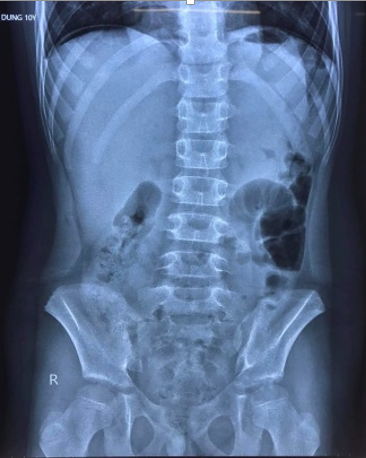

Ngày 22/02/2022, Bệnh viện Trẻ em Hải Phòng đã tiếp nhận hội chẩn từ xa từ Trung tâm y tế huyện Tiên Lãng 1 trường hợp: Bệnh nhi 10 tuổi dương tính với SARS-CoV-2, xuất hiện đau bụng dữ dội vùng trên rốn kèm sốt, nôn 1 ngày, chụp X-quang có hình ảnh liềm hơi dưới vòm hoành 2 bên, nghi ngờ thủng tạng rỗng. Nhận thấy đây là một trường hợp cấp cứu ngoại khoa cần phải xử trí kịp thời nên bệnh viện đã chỉ đạo chuyển bệnh nhân lên Bệnh viện Trẻ em Hải Phòng để điều trị.

Tại khoa truyền nhiễm, sau khi tiếp nhận bệnh nhân các bác sỹ khoa Ngoại Tổng hợp đã tiến hành thăm khám, làm các xét nghiệm và nhanh chóng chẩn đoán: Viêm phúc mạc do thủng dạ dày/Nhiễm SARS-CoV-2. Trẻ đã được tiến hành cấp cứu phẫu thuật nội soi khâu lỗ thủng dạ dày, làm sạch, dẫn lưu ổ bụng tại phòng mổ áp lực âm của khu điều trị Covid-19.